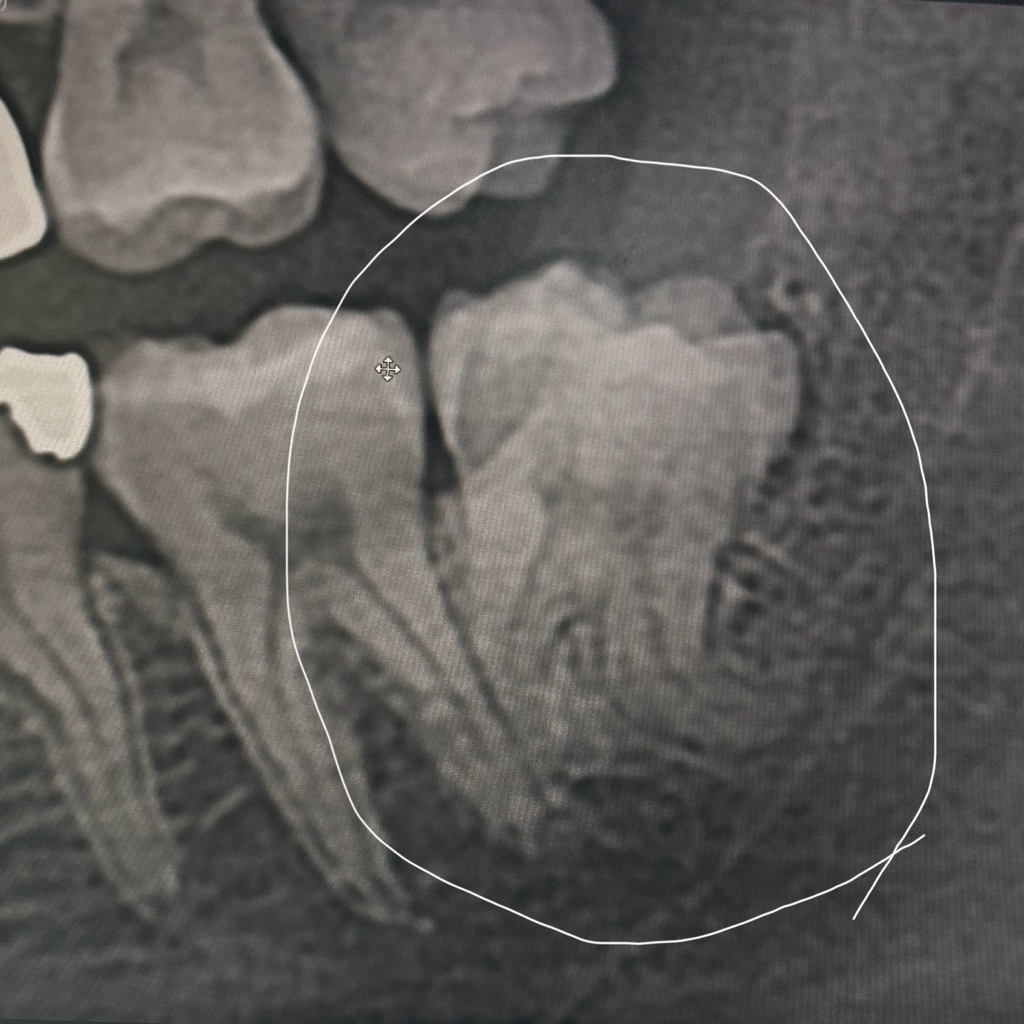

사랑니가 보기 드물게 났다고 하더라구요

신경과도 너무 가깝다고...신경 손상이 있을 수 있다는데

그래서 뿌리가 무조건 부러진다고 뿌리 부분은

남겨둔채로 발치 한다는데

• 1번 째 사진